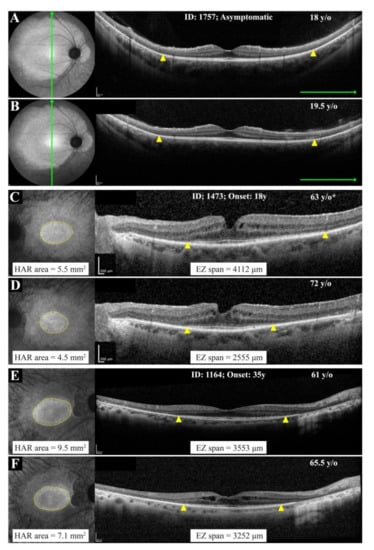

3.3. Natural History of Disease Progression

3.4. Phenotype Patterns

| 1757 | 18 | M | - | 84 (20/20) | 83 (20/25) | Clear | Clear | c.772_773delins16 | C | |

| 0725 | 1164 | 61 | F | 35 | 70 (20/40) | 70 (20/40) | IOL (58) | IOL (58) | Exon 2–8del | C |